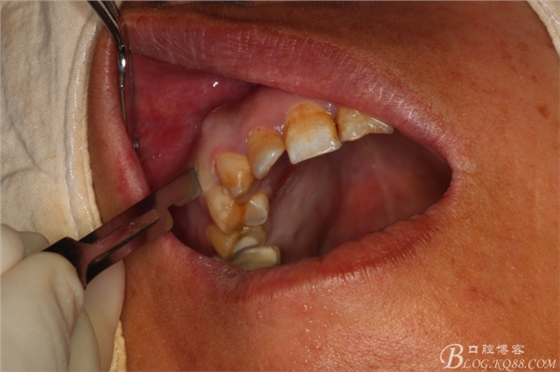

圖7.做角形切口

圖8.翻瓣